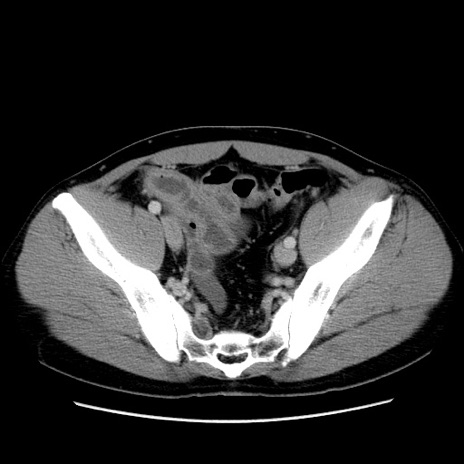

症例4(横断像)

【症例】30歳代男性

【主訴】腹痛、嘔吐

【現病歴】昨晩から突然の腹痛あり、その後嘔吐、軟便も出現。腹痛が改善しないため救急搬送となる。2日前にしめ鯖の食事歴あり。

【身体所見】意識清明、苦悶様、BP 135/90mmHg、BT 35.7℃、腹部:平坦、やや硬、心窩部〜臍部に自発痛、圧痛あり、筋性防御+、反跳痛-

【データ】WBC 8100、CRP 0.57